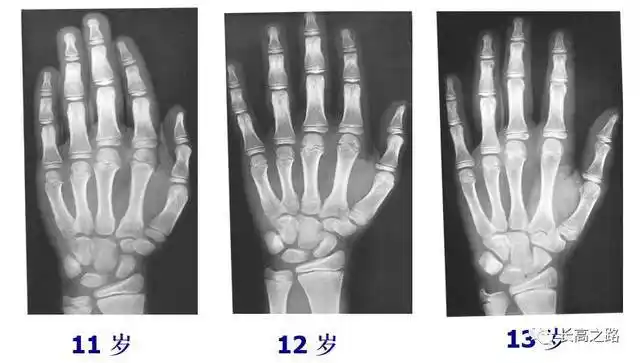

中国儿童标准骨龄片

教你简单识别孩子的骨龄片

12岁的孩子出现这样的骨龄(14岁),孩子身高目前只有148cm,预计成年

骨龄图

十二岁半男孩的骨龄,请懂的人帮我看一下